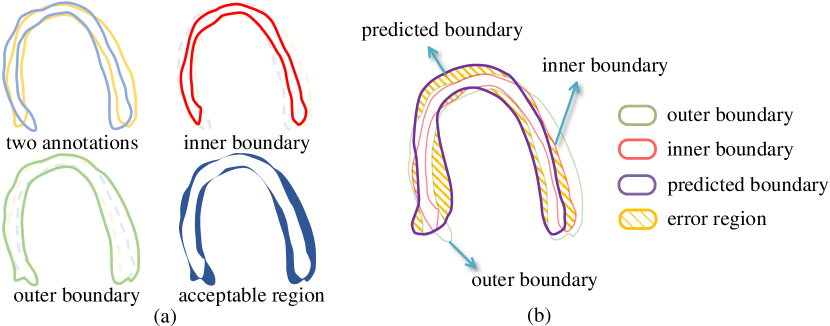

For simplicity of discussion, we use myocardial boundary annotations from two cardiologists as an example. The same concept can be readily extended to more cardiologists. We first obtain an inner boundary and an outer boundary based on these two annotations, as shown in Fig. 2(a). The inner boundary is defined by that of the intersection of the two regions enclosed by the annotated boundaries. In other words, every pixel inside the inner boundary is labeled as myocardium by both of the cardiologists. The outer boundary is that of the union of the two regions, i.e., every pixel inside the outer boundary is labeled as myocardium by at least one cardiologist. As both annotations are acceptable based on our assumption, we can obtain an acceptable region, which is the region between the inner boundary and outer boundary. The pixels inside the acceptable region can be classified as either myocardium or background; any boundary that completely falls inside the acceptable region shall be considered acceptable. Intuitively, in light of the existence of multiple acceptable annotations, the introduction of acceptable region can allow the prediction boundary to have some flexibility in regions where significant large inter-observer variability exists. Such flexibility will potentially lead to better overall segmentation quality.

Based on the observation above, we can extend the traditional Dice metric which is based on a single ground truth. Denote the region enclosed by the inner boundary and the outer boundary as and , respectively. The region inside the predicted boundary is . Then our metric can be calculated as

| (1) |

A simple illustration is shown in Fig. 2(b). We can easily see that the metric is penalizing the total segmented region outside the outer boundary and inside the inner boundary . The denominator helps scale the final result to range . We can see that if the predicted boundary is completely inside the acceptable region, the metric is 1. Otherwise, if it has no overlap with the acceptable region, the metric is 0.

Relationship to Dice: Notice that our metric can be simplified into

| (2) |

When multiple annotators give the same annotation results, which means the ground truth annotation is known and the inner boundary and the outer boundary completely overlap, the proposed metric will become the conventional Dice. Therefore, it can be viewed as extended Dice.

Once we have the proposed metric, we can further use it as a loss function to train a neural network to help the model focus more on the general features of myocardium and ignore variations from the individual cardiologist for better performance. We denote the pixel-wise annotation of the regions enclosed by the inner boundary and the outer boundary as and , and the prediction for the myocardium region in the training process as , respectively. is the index of pixel space . Then our extended Dice loss function is then defined as follows:

| (3) |

The idea of the introduced loss function is that, for pixels inside the acceptable region, any prediction result is reasonable and should not contribute to the loss function. For pixels outside the acceptable region, any misclassification should be penalized.